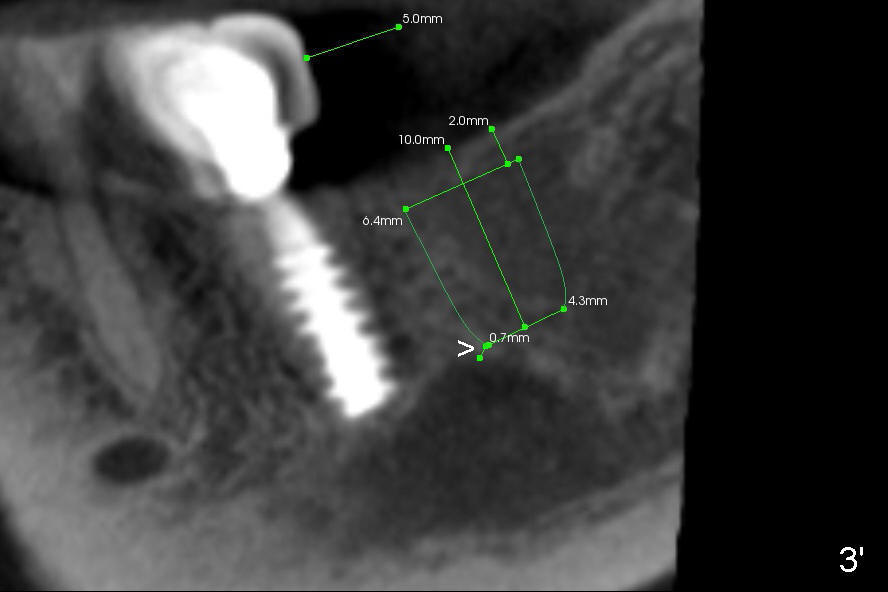

In order to bury the implant completely, the implant should be placed 2 mm below the pointed crest.  With the short implant (6.4x8 mm), there is 2 mm bone above the nerve in the coronal section (Fig.3).  It appears safe.

In the sagittal view, the implant is 0.7 mm from the bulging segment of the nerve (Fig.3' >)!